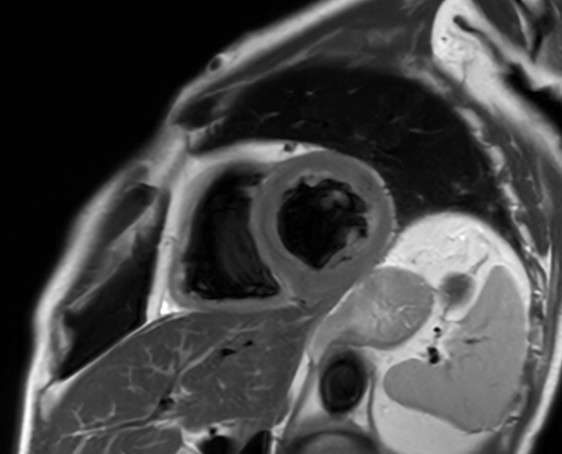

Comprehensive Cardiac with SmartSpeed Precise